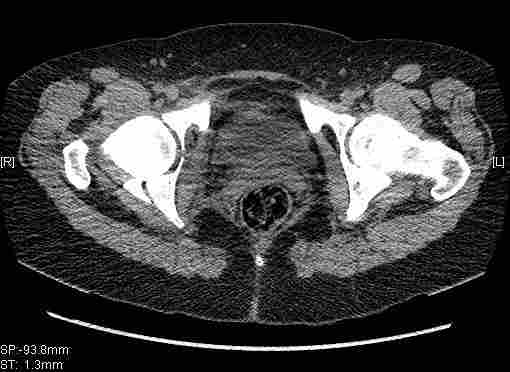

Женщина,58 лет, после ДТП 6 суток. Первично повреждение расценено как переломы ветвей лонной кости. После подтверждения повреждения вертлужной впадины,как чаще всего случается, вопрос встал о тактике. БОльшинство за консерватиное лечение.К сожалению кт у нас "во время" сломался. Прилагаю стандартные снимки вертлужки. У меня следующие вопросы к коллегам:1. Правильно ли рассценивать это повреждение как Т-образный перелом вертлужнй впадины?2. Можно ли добиться анатомической репозиции поверхности вертлужной впадины скелетным вытяжением в данном случае, если нет, что будет этому препятствовать?3. Если смещение останется таким как сейчас, через какое время появится необходимость эндопротезирования (по вашему опыту)?Спасибо.

Удалось сегодня вывести пациентку в соседнюю больницу, где есть кт. Срезы сделаны только горизонтальные.

|